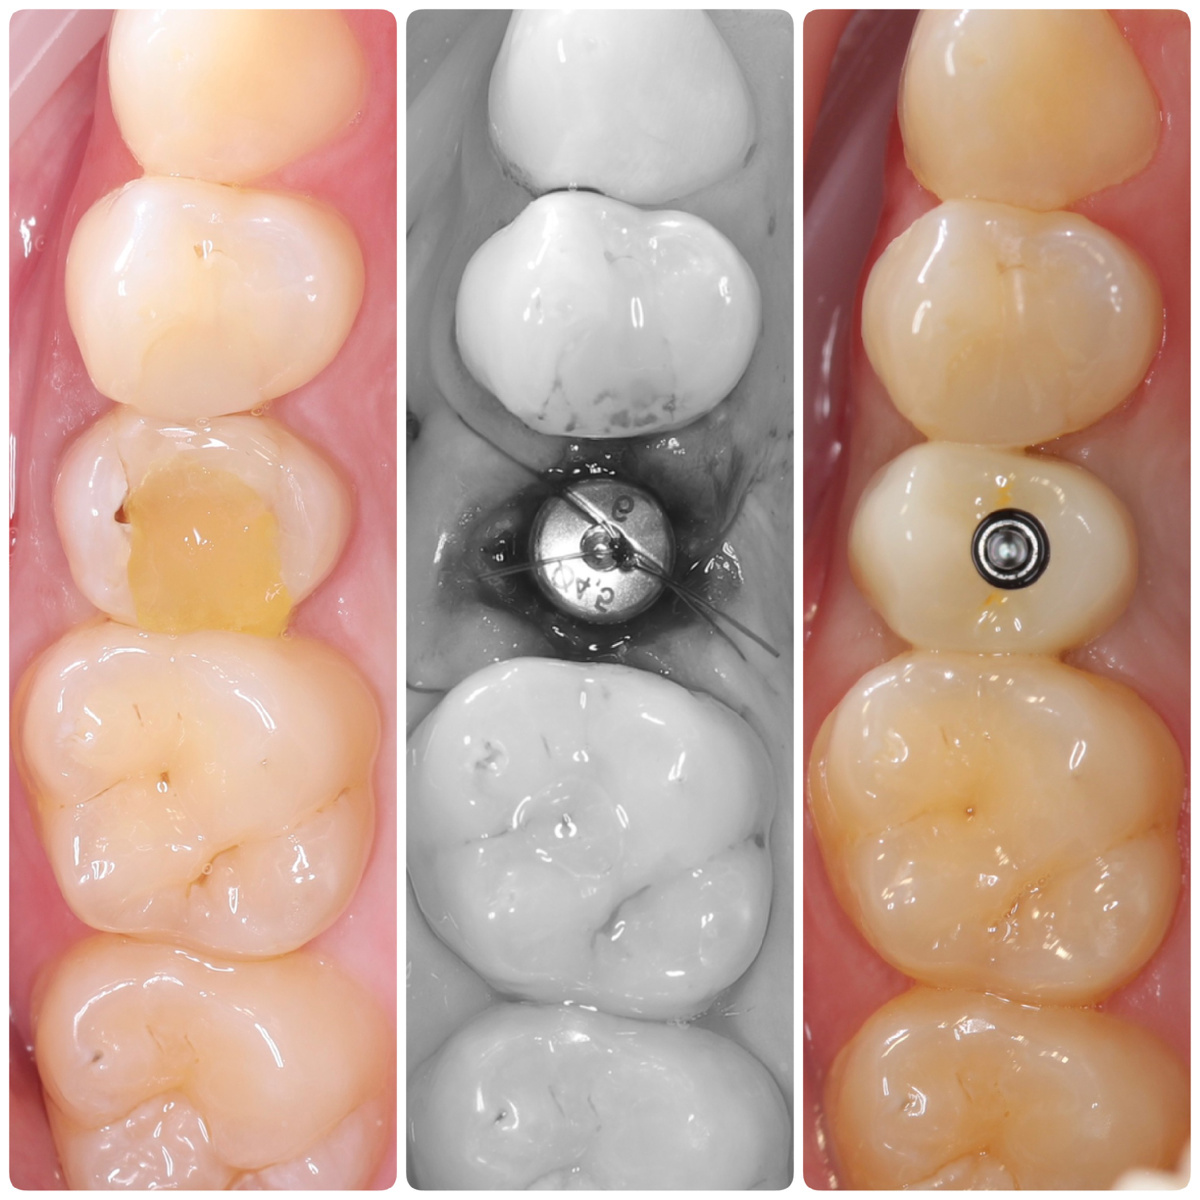

Одномоментная имплантация в области 2.5 зуба и постоянная коронка. До / после операции / после фиксации постоянной коронки (через 3 месяца)

Постоянная коронка из диоксида циркония на винтовой фиксации